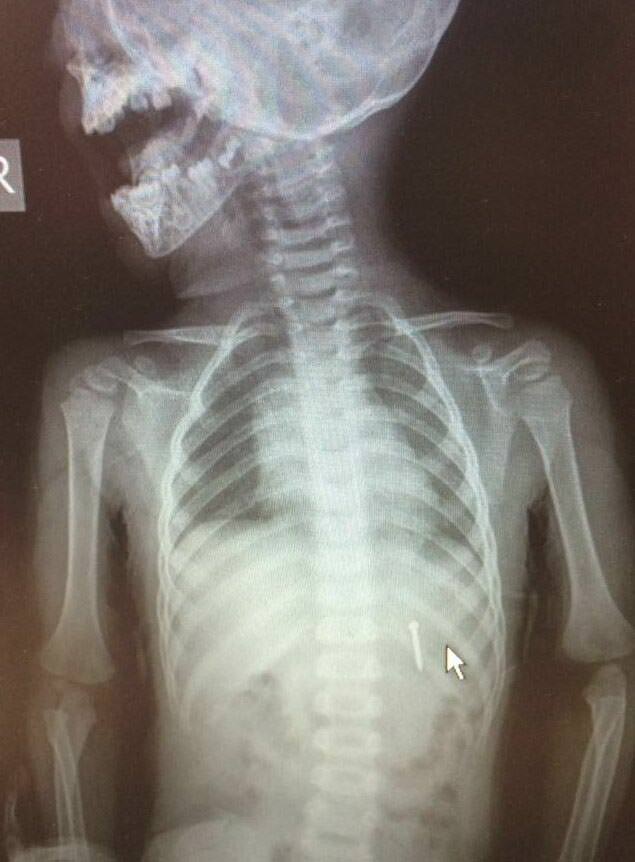

İzmir'deki Tepecik Eğitim ve Araştırma Hastanesi Çocuk Gastroenteroloji Bölümü'nün, yabancı cisim yutan çocukların nefes ve borusu ile midelerinden çıkarttığı, anahtarlık, madeni para, saat pili, ataç, çengelli iğne ve çivi gibi objeler görenleri şaşkına çevirdi.

"Çocukların nefes ve borusu ile midelerinden çıkartılan, anahtarlık, madeni para, saat pili, ataç, çengelli iğne ve çivi gibi objeler görenleri şaşkına çevirdi. "